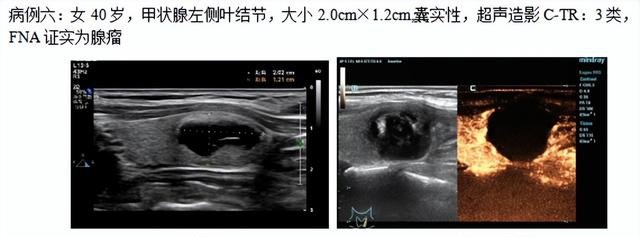

近期,石门县中医医院介入超声门诊成功开展甲状腺射频消融术6台(2例良性、4例甲状腺微小乳头状癌),术中、术后行超声造影检查,肿瘤消融完全患者总住院天数为2天,微创、无痛、并发症小、后期恢复快。

消融病例